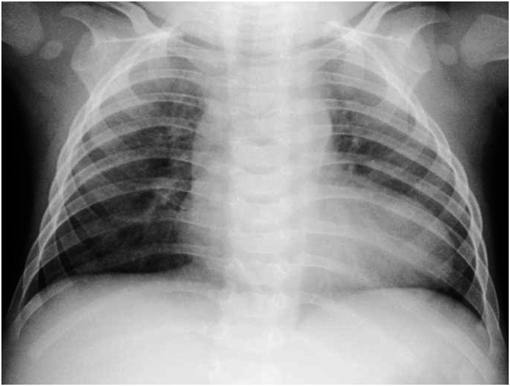

生後6ヶ月の胸部X線では心胸郭比63.0%と改善した(Fig. 6).生後9ヶ月時にMRは軽度と悪化なく,心機能良好のため,ジゴキシンの内服を中止した.1歳時の心臓超音波検査では僧帽弁の両尖に肥厚と前尖(A2)に軽度逸脱を認め,MR軽度でA2と前交連より吹く,TR軽度,LVEF 72.2% LVDd 24.6 mm(Fig. 7)と悪化なく,発達も正常で外来経過観察中である.

Fig. 6 Chest X-ray at 6 months old

Chest X-ray shows slight cardiomegaly.

Pediatric Cardiology and Cardiac Surgery 33(3): 215-220 (2017)

Fig. 7 Echocardiogram at one year

(A) and (B) show mild mitral and tricuspid regurgitation.